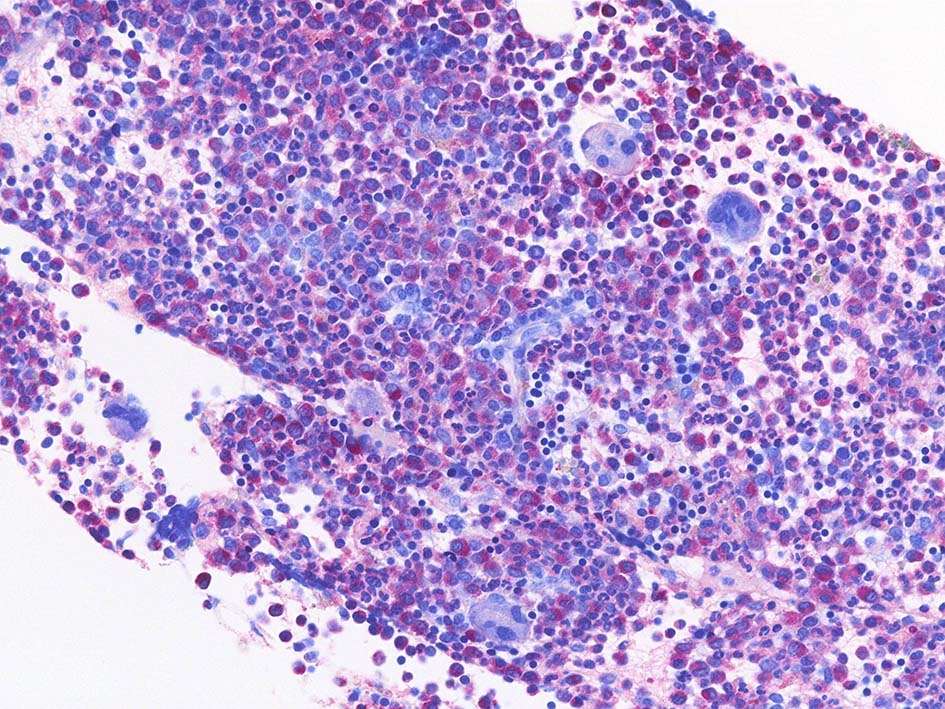

Naphtohl-ASD-CAE Fig.02

Fig.01: hypercellular marrow. ASDで赤染する細胞の増加=granulopoietic hyperplasiaがある.

Fig.02: 幼若な顆粒球が増加している. 赤芽球は散在しており血島は不明瞭である. 過形成髄なのにFig.02に成熟大型巨核球はみられない.

Fig.03: granulopoietic hyperplasia. 成熟顆粒球の増加もある.

- ASD-Giemsa: 巨核球は大型であるが, 低分葉や異常な分葉, 分離核Mgkなどが認められる.

- CD42b; microMgkは増加してない. hypercellular marrowであるがMgkの増加はみられない.